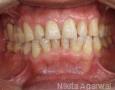

Pictures

Baseline